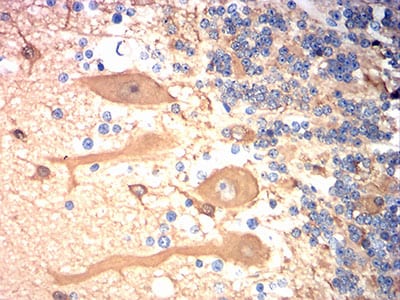

Immunohistochemical analysis of paraffin-embedded human cerebellum tissues using TUBB3 mouse mAb with DAB staining.